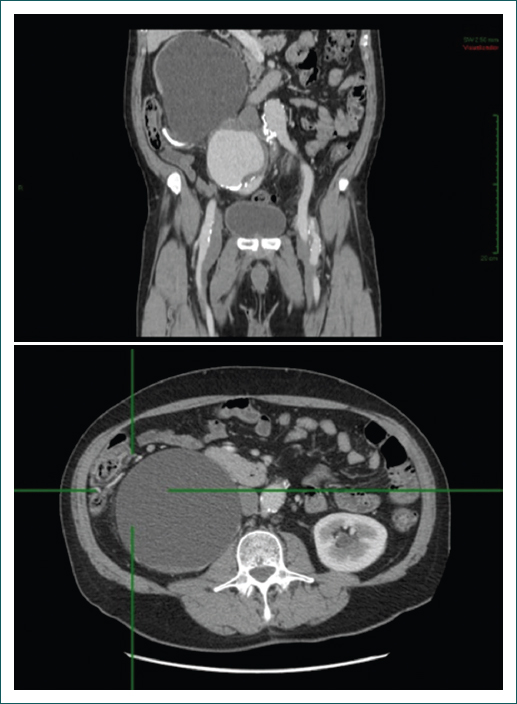

Su padecimiento actual inició 20 días previos a su internamiento, presentando de manera súbita dolor de tipo punzante, intermitente, localizado en la fosa renal derecha, inicialmente de intensidad 4/10 y que aumentó de manera progresiva a 10/10, que irradiaba a la extremidad inferior homolateral, sin exacerbantes ni atenuantes, y acompañado de disuria y polaquiuria. Acudió al urólogo, quien solicitó una tomografía computada contrastada abdominal y pélvica, que evidenció tres aneurismas localizados en las arterias ilíacas común derecha e interna y externa izquierdas, además de quistes renales bilaterales de predominio derecho (Fig. 1).

En la exploración física se encontró hipertenso (140/100 mmHg), con dolor abdominal a la palpación media y profunda en hipogastrio y mesogastrio irradiado al miembro pélvico, con sensación de masa pulsátil y soplo en la misma región e irradiado al flanco derecho, hiperalgesia en la región inguinal derecha y con pulsos periféricos de miembros inferiores disminuidos en intensidad, sobre todo del lado derecho. Se le realizó una angiotomografía, la cual corroboró tres aneurismas: uno en la arteria ilíaca común derecha de 10 × 9 cm con trombo mural, y los otros dos en las arterias ilíacas interna y externa izquierdas, de 5 × 5 cm y 3 × 2 cm, respectivamente; además de quistes renales bilaterales de predominio derecho y litiasis renal, lo que explica las manifestaciones urológicas (Fig. 2).